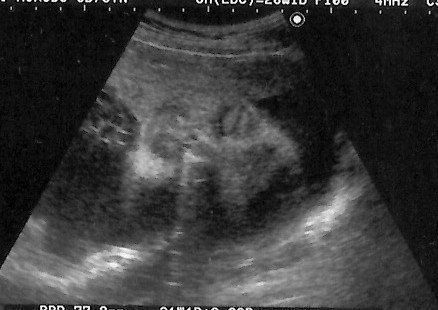

妊娠31週目のエコー写真 3Dエコー画像撮影に再チャレンジ

以前の3D画像撮影で赤ちゃんの顔の撮影ができなかったことがどうしても心残りで、義理の母が上京するタイミングに合わせて再撮影にチャレンジ。病院からは、この時期は赤ちゃんが育ちすぎているので希望通りに撮影できるかわかりません、と言われていました。それでも撮影中は、看護師さんが寝ている赤ちゃんをおなかの上から優しくゆすって顔の位置を変えてくれ、無事撮影することができました。